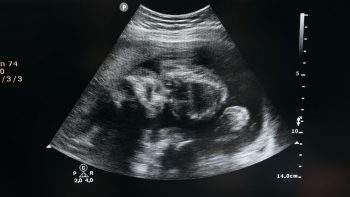

Hệ thống trang thiết bị, máy móc, dụng cụ y tế hiện đại, tối tân, được nhập khẩu từ những nước phát triển trên thế giới, giúp hỗ trợ các bác sĩ kiểm tra tuổi thai, chẩn đoán chính xác, tránh gây tổn thương tử cung.